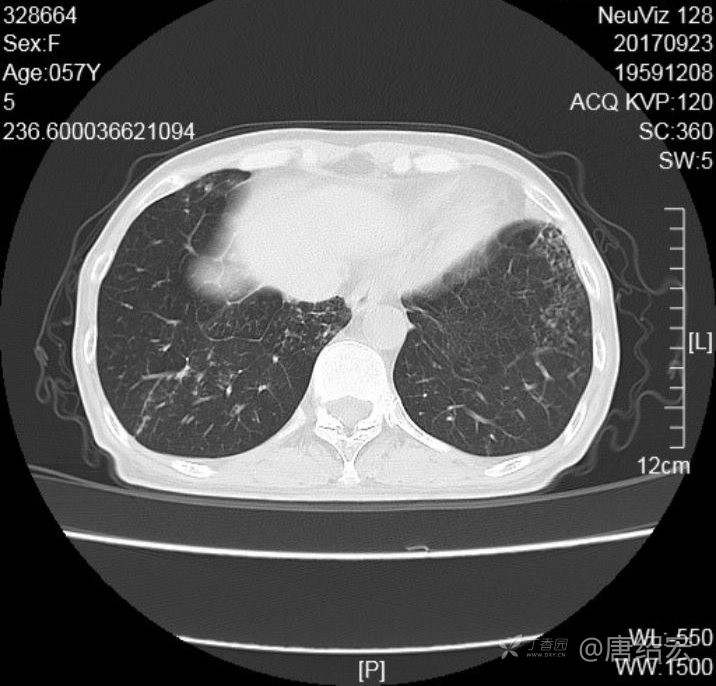

中年女性满肺树芽征还有支气管扩张,考虑什么疾病?

女,57岁,

主诉:发热、咳嗽、咯黄痰,胸闷3天入院。